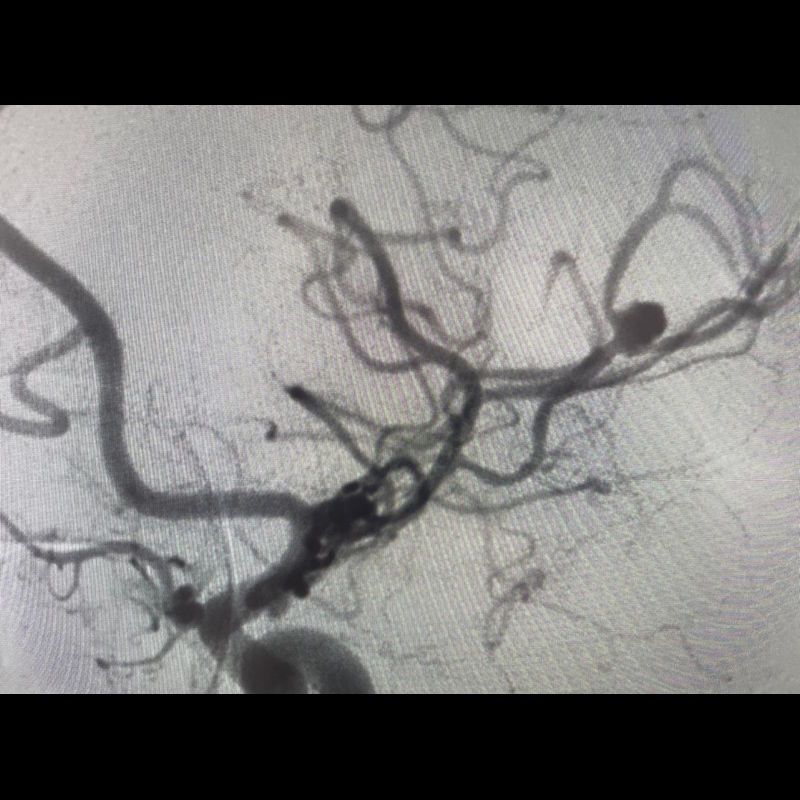

40 yaş, K

Ateş, bir haftadır artan baş ağrısı, yeni gelişen bilinç bulanıklığı

Sol MCA Segmet M2-3’te Sakküler Mikotik Anevrizma Rüptürü

Enfekte intrakraniyal anevrizma rüptürü